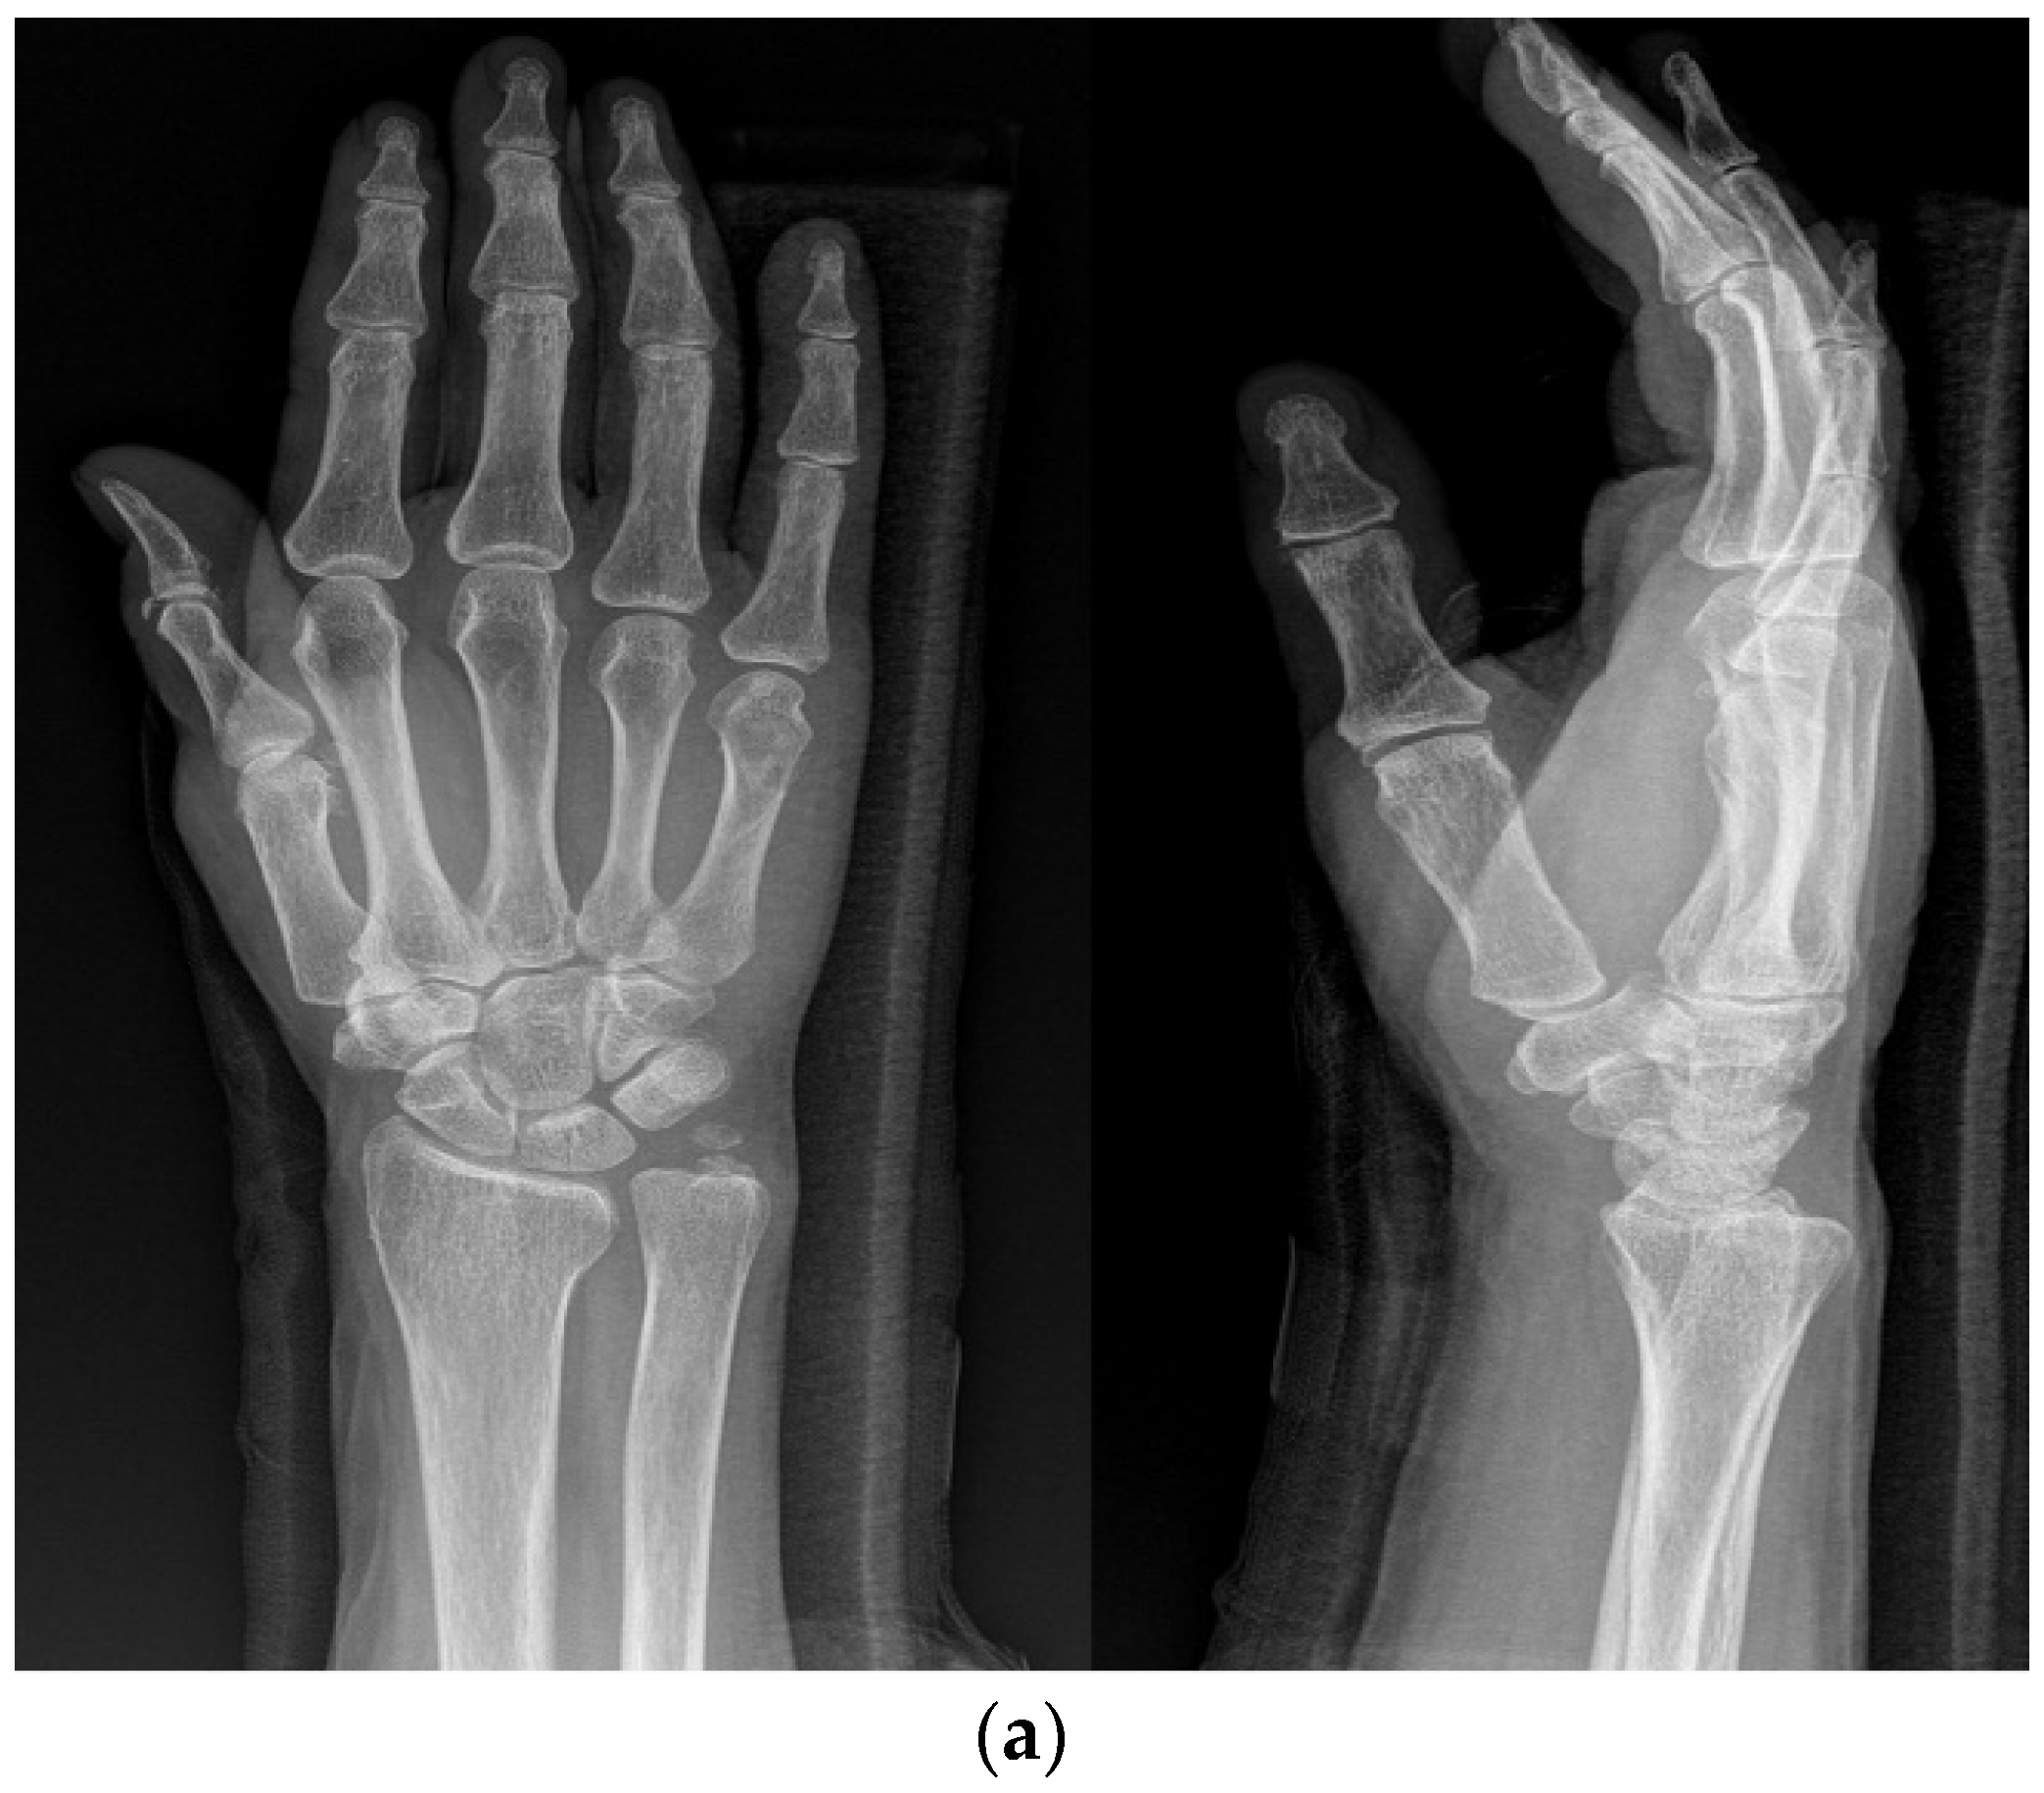

A comparative evaluation study was undertaken to assess the relative efficacy of three distinct treatment modalities for fractures in the fifth-metacarpal neck, namely, the K-wire pinning (KP) method, the intramedullary pinning (IP) method, and the combined intramedullary pinning with K-wire pinning (IPKP) method. Surgery using one of these three methods was decided upon based on the surgeon’s preference. Conducted as a retrospective study at a single center, this study’s duration spanned from January 2005 to April 2023, utilizing medical records and radiographic images as the primary data sources. The inclusion criteria for this study sought patients aged 18 years or older with a diagnosis of a fifth-metacarpal neck fracture exhibiting angulations exceeding 40° (the normal range of angulation is <15°) [5,6]. The availability of complete medical records and radiographic images after a minimum follow-up of 1 year was also considered.

All patients were clinically assessed using the Quick-DASH questionnaire, and a cosmetic score was obtained using the SBSES score at 12 months post-operation. The active ranges of motion (ROM) of the MP, PIP, and DIP joints were recorded using a flat, 5.5-inch-long, stainless-steel finger goniometer (Baseline®, Fabrication Enterprise Inc., White Plains, NY, USA), from which the total active motion (TAM) was calculated. Following the guidelines of the American Association of Orthopedic Surgery, full range of motion (ROM) was measured at 280 degrees. For this study, we chose to classify patients experiencing a ROM of 70% or less as exhibiting stiffness. Radiographic images were assessed by two orthopedic surgeons and acquired preoperatively, immediately postoperatively, and 12 months after surgery. The images included an anteroposterior (AP) view, a lateral oblique hand X-ray, and the dorsal apex angle (DAA) to determine angulation and shortening. Rotational deformity was clinically assessed with overlapping fingers, while a clenched fist showed a considerable degree of rotation. Furthermore, alignment could be assessed by examining the hand with the MCP and PIP joints in flexion and DIP joints extended. If lines drawn along the digits did not converge toward the others, we considered it a rotational deformity [7]. To calculate the shortening of the 5th metacarpal, a line was drawn through the most distal point of the heads of the neighboring 3rd and 4th metacarpals. The shortening was defined as the distance from this line to the most distal point of the fractured 5th metacarpal bone. The patients were instructed to complete the questionnaires at our clinic at 1-year follow-up visits. Functional outcomes and patient-reported disabilities were assessed using the Quick Disabilities of the Arm, Shoulder, and Hand (Quick-DASH) score. Lower scores on these assessments indicate superior functional outcomes and reduced disability. Additionally, patients rated their cosmetic satisfaction on a scale from 1 to 5, where higher scores denoted greater contentment with their cosmetic outlooks.